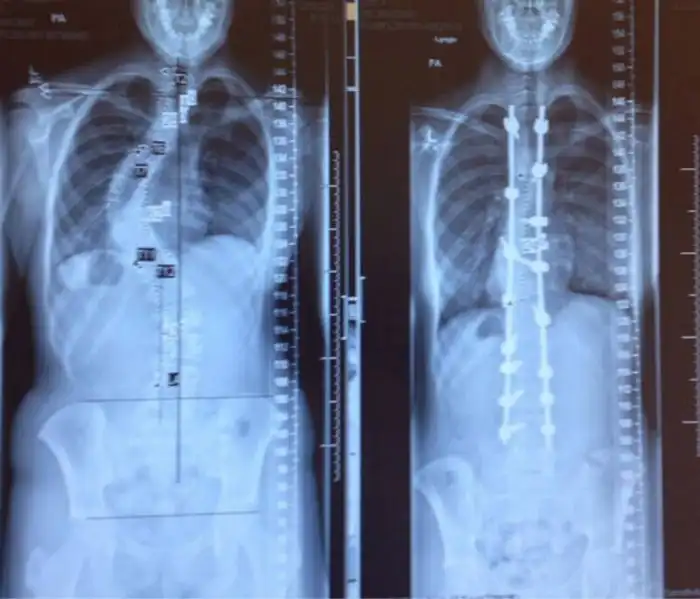

Рентген позвоночника до и после лечения сколиоза